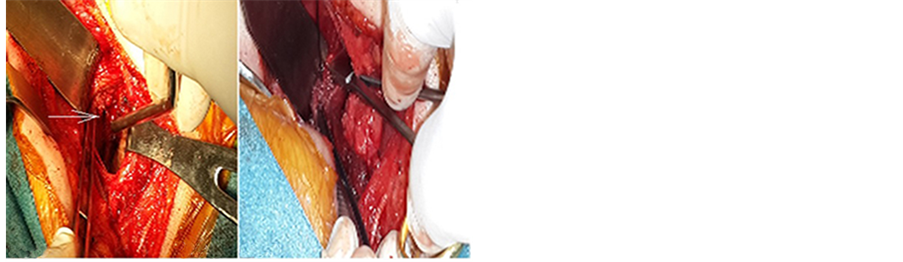

The infected disc was removed in a piecemeal fashion. The posterior longitudinal ligament had been breached by the abscess which was removed in total after drilling of both endplates and part of the vertebral bodies of C2 and C3, leading to adequate spinal cord decompression (Figure 4). Fusion was done using autologus bone graft harvested from the right iliac crest (Figure 5).

The sternocleidomastoid was carefully dissected along its length. The greater auricular nerve was identified and spared. The medial half of the muscle was separated from the bulk of the muscle and cut inferiorly, creating a superiorly-based muscle flap (Figure 6).

Figure 4. C2 C3 disc space after evacuation of the abscess and drilling of lower endplate of C2 and upper endplate of C3.

Figure 5. Fusion of C2 C3 using autologus bone graft harvested from right iliac crest.

Figure 6. Muscle flap from sternocleidomastoid muscle.